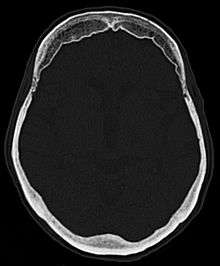

Hyperostosis frontalis at CT

Hyperostosis frontalis interna is a common, benign thickening of the inner side of the frontal bone of the skull. It is found predominantly in women after menopause and is usually asymptomatic. Mostly frequently it is found as an incidental finding discovered during an X-ray or CT scan of the skull.